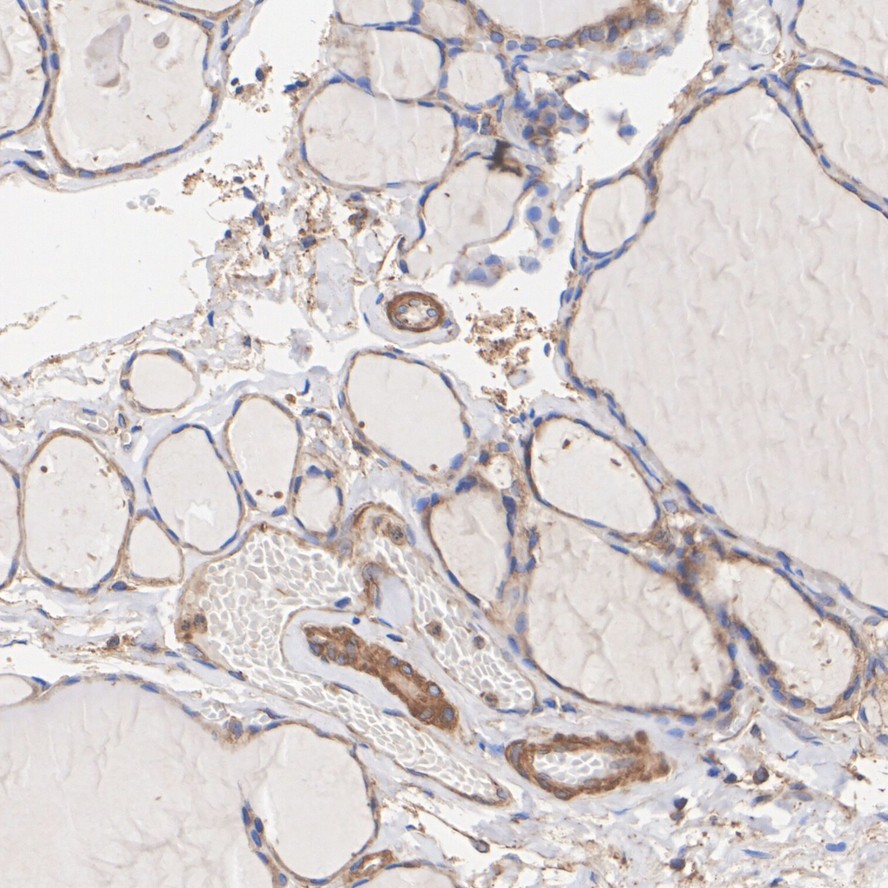

Immunohistochemical analysis of paraffin-embedded mouse thyroid tissue with Rabbit anti-ROCK1 antibody (ET1609-53) at 1/200 dilution.

The section was pre-treated using heat mediated antigen retrieval with Tris-EDTA buffer (pH 9.0) for 20 minutes. The tissues were blocked in 1% BSA for 20 minutes at room temperature, washed with ddH2O and PBS, and then probed with the primary antibody (ET1609-53) at 1/200 dilution for 1 hour at room temperature. The detection was performed using an HRP conjugated compact polymer system. DAB was used as the chromogen. Tissues were counterstained with hematoxylin and mounted with DPX.